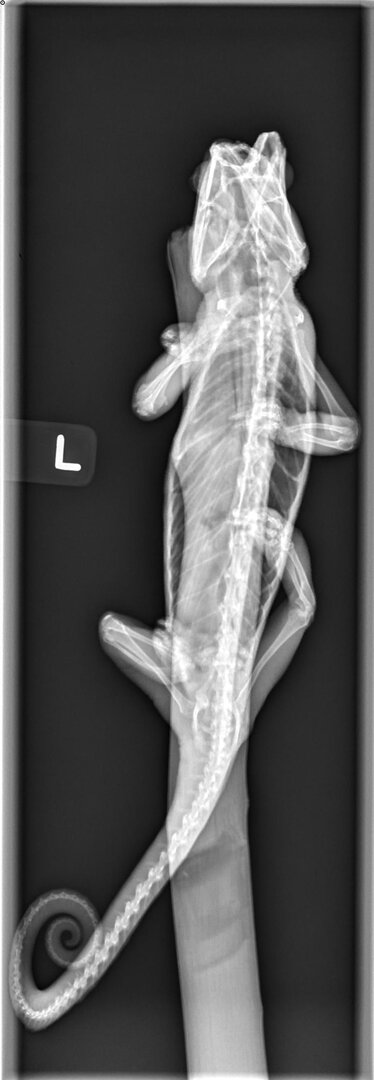

Here are Squirt's Xrays. I don't know how to look at those, but I'm worried about his tail. I think the rest of his parts look good.

• Newman,Squirt10.30.200001.jpg

Newman,Squirt10.30.200001.jpg

43.6 KB · Views: 169

• Newman,Squirt10.30.200002.jpg

Newman,Squirt10.30.200002.jpg

218.9 KB · Views: 156

• Newman,Squirt10.30.200003.jpg

Newman,Squirt10.30.200003.jpg

42 KB · Views: 169